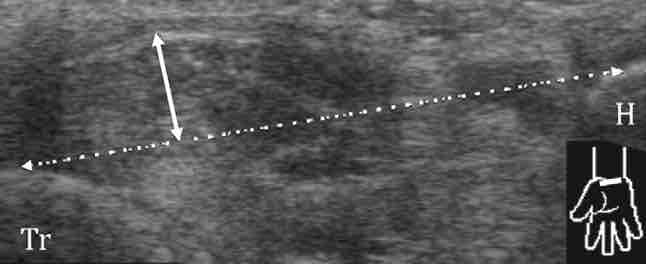

sd canal carpien = nerf > 12-15 mm², index d'aplatissement > 3,

sd canal carpien = nerf > 12-15 mm², index d'aplatissement > 3,nerf hypo +/- signal Doppler, bombement rétinaculum > 4 mm,

Pas d'anomalie des nerfs médian et ulnaire au poignet.